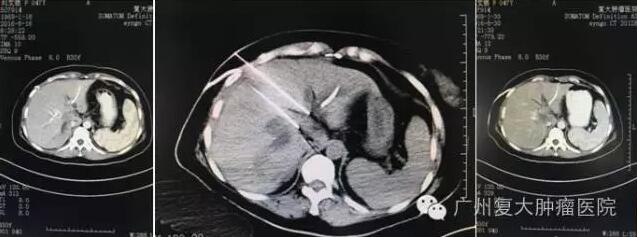

图1(术前):肝门区间可见不规则肿块。

图2(术中):治疗过程CT影像:纳米刀两根电极针插入肿块两侧

图3(术后):纳米刀治疗后一周复查,CT影像是肝门区全部坏死,病灶范围缩小。